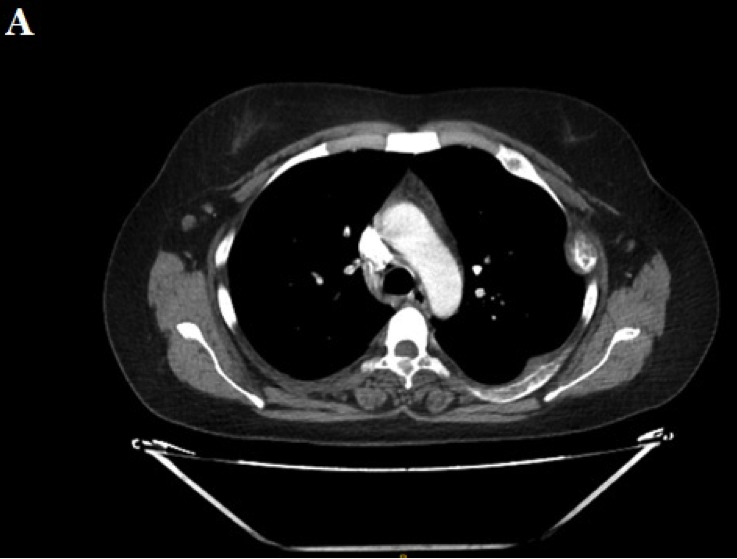

Ante la sospecha clínica de tumores pardos múltiples versus enfermedad metastásica se realiza IC con Oncología y en conjunto se solicitaron los siguientes estudios, que informaron como positivo: a) TAC de tórax, abdomen y pelvis (con contraste): leve enfisema centrolobulillar bilateral, opacidades nodulares con densidad de partes blandas (LSD y LSI). Resto de los órganos normales, no adenomegalias. Presencia de múltiples lesiones osteolíticas a nivel de todos los cuerpos vertebrales, esternón, región anterior de varias costillas, húmero, sacro, y porción visible de ambos ilíacos (Figuras 2, 3 . 4 A); b) TAC de cuello (con contraste): múltiples lesiones osteolíticas en la columna cervical.